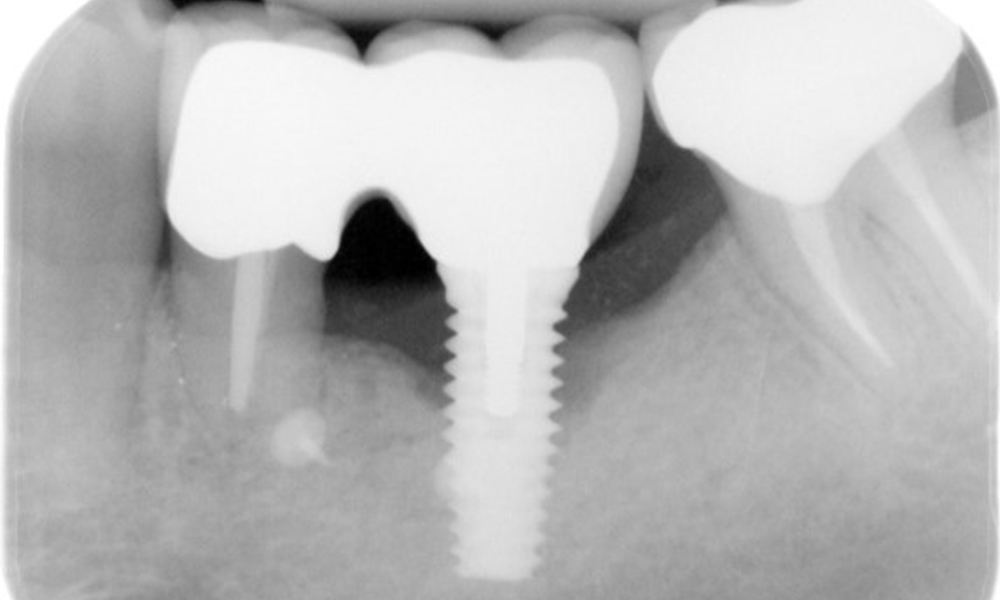

The patient has no particular risk factors with specific dental implications in his medical history. The key factor, therefore, is the requirement in terms of oral health. In this respect, there is evidence of a probing depth of 5 mm at the implant in the 3rd quadrant and, on the X-ray image, increased bone loss. The patient also has currently stable early periodontal disease and two active initial carious lesions.

The X-ray images show the progression of bone loss.

The X-ray images show the progression of bone loss in the area of the implant in region 36: dental film from 11.02.2021 (left) and dental film from 18.01.2024 (right).